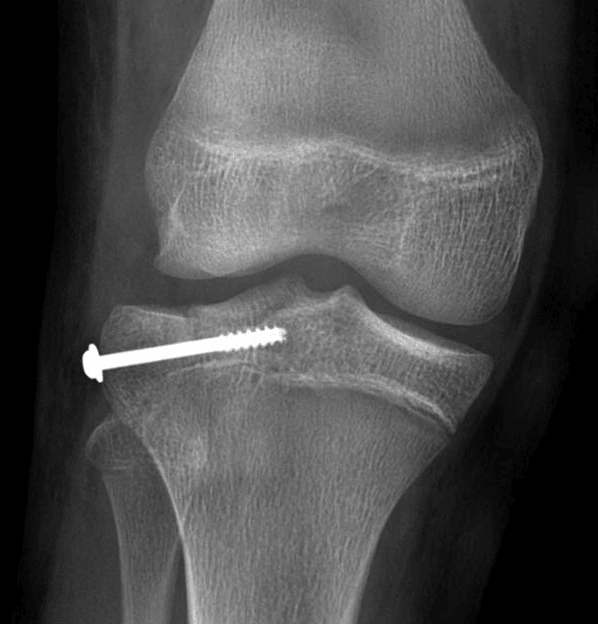

Postoperative radiograph in this patient.